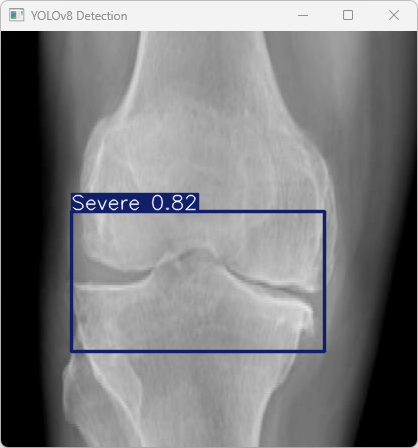

执行imgTest.py代码后,会将执行的结果直接标注在图片上,结果如下:

这段输出是基于YOLOv8模型对图片“imagetest.jpg”进行检测的结果,具体内容如下:

图像信息:

(1)处理的图像路径为:TestFiles/imagetest.jpg。

(2)图像尺寸为640×640像素。

检测结果:

(1)检测到图像中的骨折类别为Severe(严重骨折)。

处理速度:

(1)预处理时间: 5.0 毫秒

(2)推理时间: 4.5 毫秒

(3)后处理时间: 68.7 毫秒

总结:

YOLOv8模型成功检测到图像中的严重骨折类别,并且推理过程在速度上表现非常高效,整体响应时间较短。推理所需的时间包括图像预处理、模型推理和结果后处理,这些时间对实时应用是非常友好的。